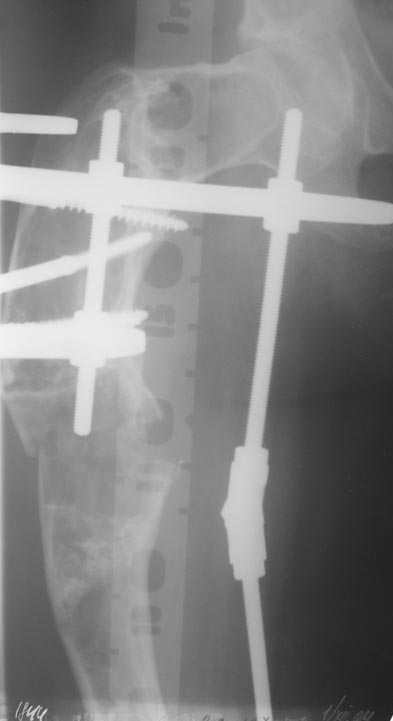

Уважаемые коллеги! Большое спасибо за живой отклик и предложения по тактике лечения. Больной произведен первый этап - стержневой аппарат издвух баз, кортикотомия, остеоклазия и начата коррекция в аппарате. Почти исправлен угол, не сегодня укорочение 2см. Когда завершим коррекция, представлю рентгенограммы.

Leonid Pollyak 02 Январь 2005, 22:42

В ноябре этого года я обращался с просьбой о помощи в выборе тактики лечения больной с деформацией бедра на почве фиброзной дисплазии. Были получены интересные и очень полезные советы по операции.

Хотелось бы показать, что получилось в результате.

Операция выполнялась с помощью А.Н.Челнокова. Очень понравилась технология выполнения блокируемого остеосинтеза с использованием спицевого дистрактора, модифицированный гвоздь с латерализованным проксимальным отделом и возможностью многовинтовой фиксации проксимального и дистального участков бедра.